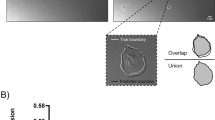

Figure 3A,B (representative images from Impact-R (i) PRE-DI, (ii) END-DI and (iii) RECOVERY-DI show the effect of physical inactivity on platelet function. There was a significant increase in platelet adhesion from PRE-DI to END-DI time points and a subsequent decrease between the END-DI and RECOVERY-DI time points. There was also a significant increase in platelet aggregation from PRE-DI to END-DI.

(A) Effect of dry immersion on platelet function assessed by Impact R analysis. Graphs represent the mean ± SEM of each parameter at each time point. (i) Platelet Adhesion and (ii) Platelet Aggregation. * P < 0.05. Paired samples t-test and repeated measures ANOVA (adjusted for age, BMI and VO2; n = 12 biological replicates, technical replicates n = 3 for each subject). (B) Impact R images from subject J at each stage of dry immersion. Image shows platelet adhesion and aggregation at (i) PRE-DI, (ii) END-DI and (iii) RECOVERY-DI.